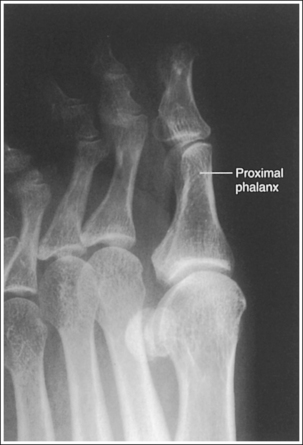

See Figures 6-5 and 6-6 and Box 6-3.

FIGURE 6-5 AP oblique toe projection with accurate positioning. DIP, Distal interphalangeal; MTP, metatarsophalangeal.

The digit(s) is rotated 45 degrees. Twice as much soft tissue width and more phalangeal and metatarsal concavity are present on the side of the digit rotated away from the IR.

• An AP oblique toe(s) projection is obtained by placing the affected foot on the IR and then rotating the foot until the affected toe is rotated 45 degrees from the AP projection (Figure 6-7). When the first through third toes are of interest, the foot should be rotated medially. When the fourth and fifth toes are of interest, the foot should be rotated laterally. The variation in rotation for the different toes is to obtain an AP oblique projection with the least amount of OID.